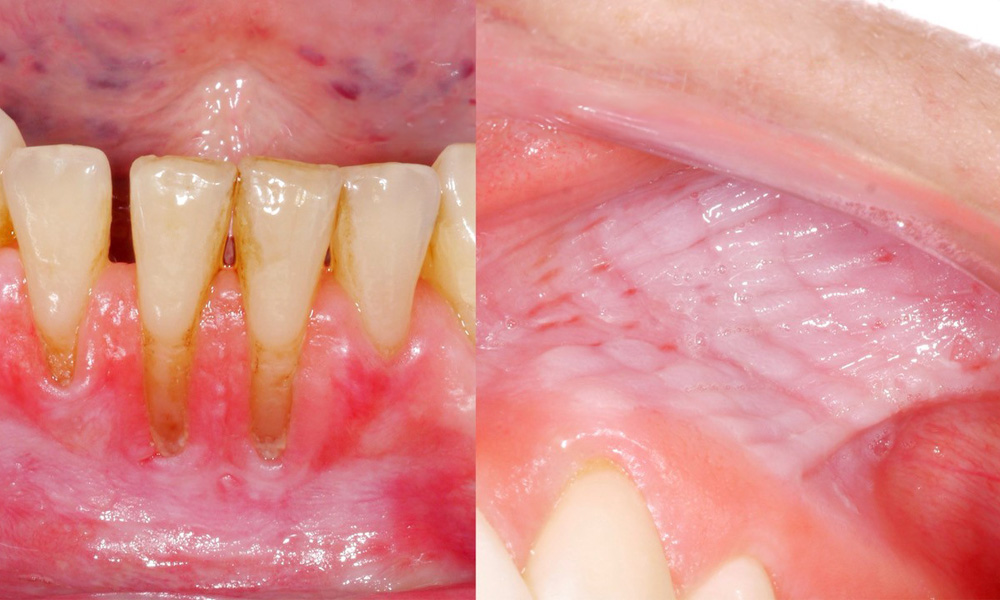

Snus causes mucosal lesions & gingival recession

The clinical examination showed that regular consumption of snus can have the following effects on the oral mucosa:

- Approximately 80% of those examined who consumed snus daily had snus-induced mucosal lesions.

- Approximately 20% of those examined who consumed snus daily had snus-induced gingival recession.